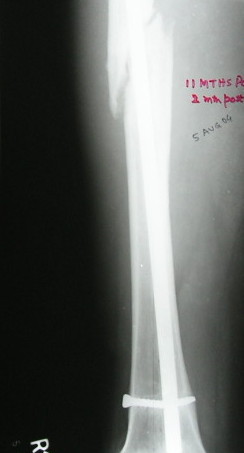

Failure to close 4/4 cortices 6 months post-op definitely meets definition criteria of non-union. Obviously, fixation has failed in this case and needs to be achieved via exchange nail.

Tough to tell from these x-rays, but fx ends appear sclerotic with bridging callus partially present - likely hypertrophic non-union, but you can do a bone scan to confirm viability.

To my knowledge, you do not have to debride or ream in those cases if angular deformity of the medullary canal allows nail passage. If you are able to compress the fracture, this should have a high rate of union.

VMI> Kindly note. a) the nail is going towards the medial aspect

VMI> of the lower end thus causing a 5* varus at the # site. b) there

VMI> is a slight overiding causing a centimeter of shortening.

It is agreed by almost all that this is a hypertrophic nonunion.

Ajit >>Also, there is insufficient callus to suggest a hypertrophic nonunion after 14 mths. As

Ajit >>mentioned by you the first surgeon has already opened the fracture site and probably

Ajit >>devitalised/ stripped the femur of its perisoteum. Adding bone grafts will surely help.

VMI- OK It is not hypertrophic but normotrophic nonunion. Mangal has already said so. Though the first surgeon has devitalised the femur, that was 14 mths ago. By the way, the second surgery (may be the same surgeon) 5 months ago may also have done some harm. Anyway there is no need to do bone grafting if everything is done closed.